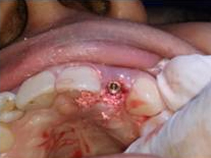

Placement of Bone Grafting

Implant with bone Graft

Suturing done